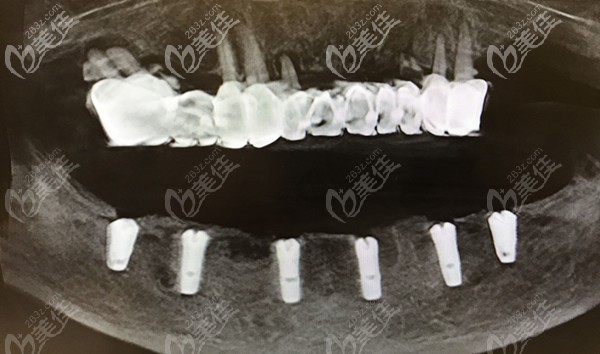

ALL-ON-4微創(chuàng)即刻種植:只需種入4顆種植體,就可以恢復半口牙的咀嚼功能,創(chuàng)傷小,出血少,并能實現(xiàn)當天種牙,當天戴牙冠吃東西。

數(shù)字化3D導板種植技術:可以在口內模擬種植,避開神經血管,設計種植方案,準確定位,減少手術時間及手術創(chuàng)傷,并且無需翻瓣種牙,使得種植手術更加舒適安 全。